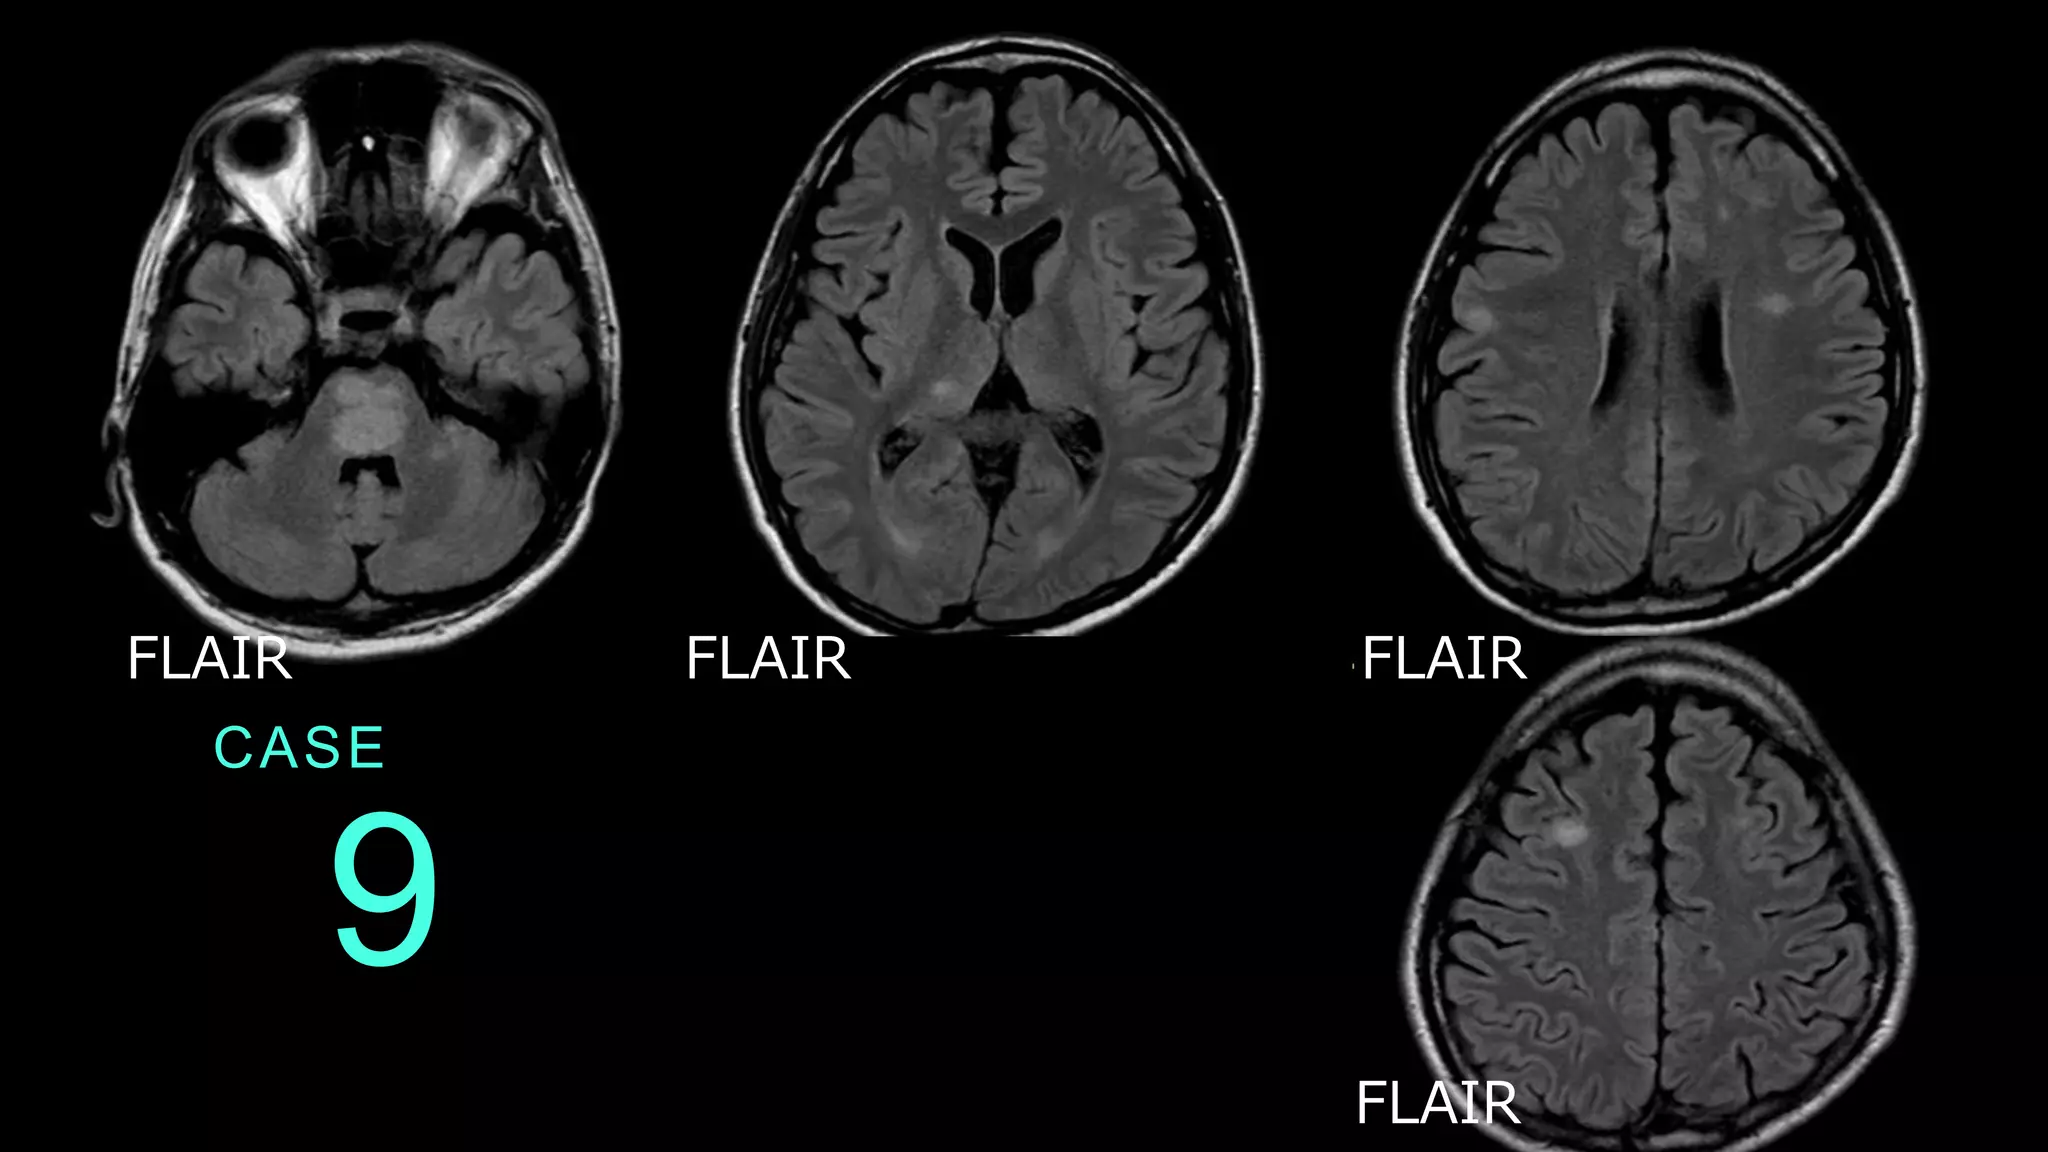

9 CASE FLAIR FLAIR FLAIR FLAIR

9 CASE FLAIRで高信号病変が散在している。脳幹、脳深部、前 頭葉白質に斑状の高信号病変が認められる。

9 CASE コメント:ADEMの症例。これも1つ提示するなら FLAIR、としてプレゼンする。一部皮質も含むが、白質 病変主体である、というニュアンスを強調している。